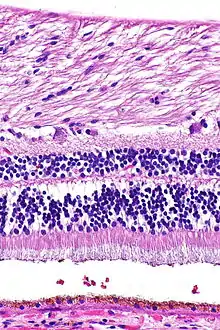

H&E is the combination of two histological stains: hematoxylin and eosin. The hematoxylin stains cell nuclei a purplish blue, and eosin stains the extracellular matrix and cytoplasm pink, with other structures taking on different shades, hues, and combinations of these colors.[5][6] Hence a pathologist can easily differentiate between the nuclear and cytoplasmic parts of a cell, and additionally, the overall patterns of coloration from the stain show the general layout and distribution of cells and provides a general overview of a tissue sample's structure.[7] Thus, pattern recognition, both by expert humans themselves and by software that aids those experts (in digital pathology), provides histologic information.

Hematoxylin principally colors the nuclei of cells blue or dark-purple,[6][15][14] along with a few other tissues, such as keratohyalin granules and calcified material. Eosin stains the cytoplasm and some other structures including extracellular matrix such as collagen[5][7][14] in up to five shades of pink.[8] The eosinophilic (substances that are stained by eosin)[5] structures are generally composed of intracellular or extracellular proteins. The Lewy bodies and Mallory bodies are examples of eosinophilic structures. Most of the cytoplasm is eosinophilic and is rendered pink.[10][15] Red blood cells are stained intensely red.

The structures do not have to be acidic or basic to be called basophilic and eosinophilic; the terminology is based on the affinity of cellular components for the dyes. Other colors, e.g. yellow and brown, can be present in the sample; they are caused by intrinsic pigments such as melanin. Basal laminae need to be stained by PAS stain or some silver stains, if they have to be well visible. Reticular fibers also require silver stain. Hydrophobic structures also tend to remain clear; these are usually rich in fats, e.g. adipocytes, myelin around neuron axons, and Golgi apparatus membranes.